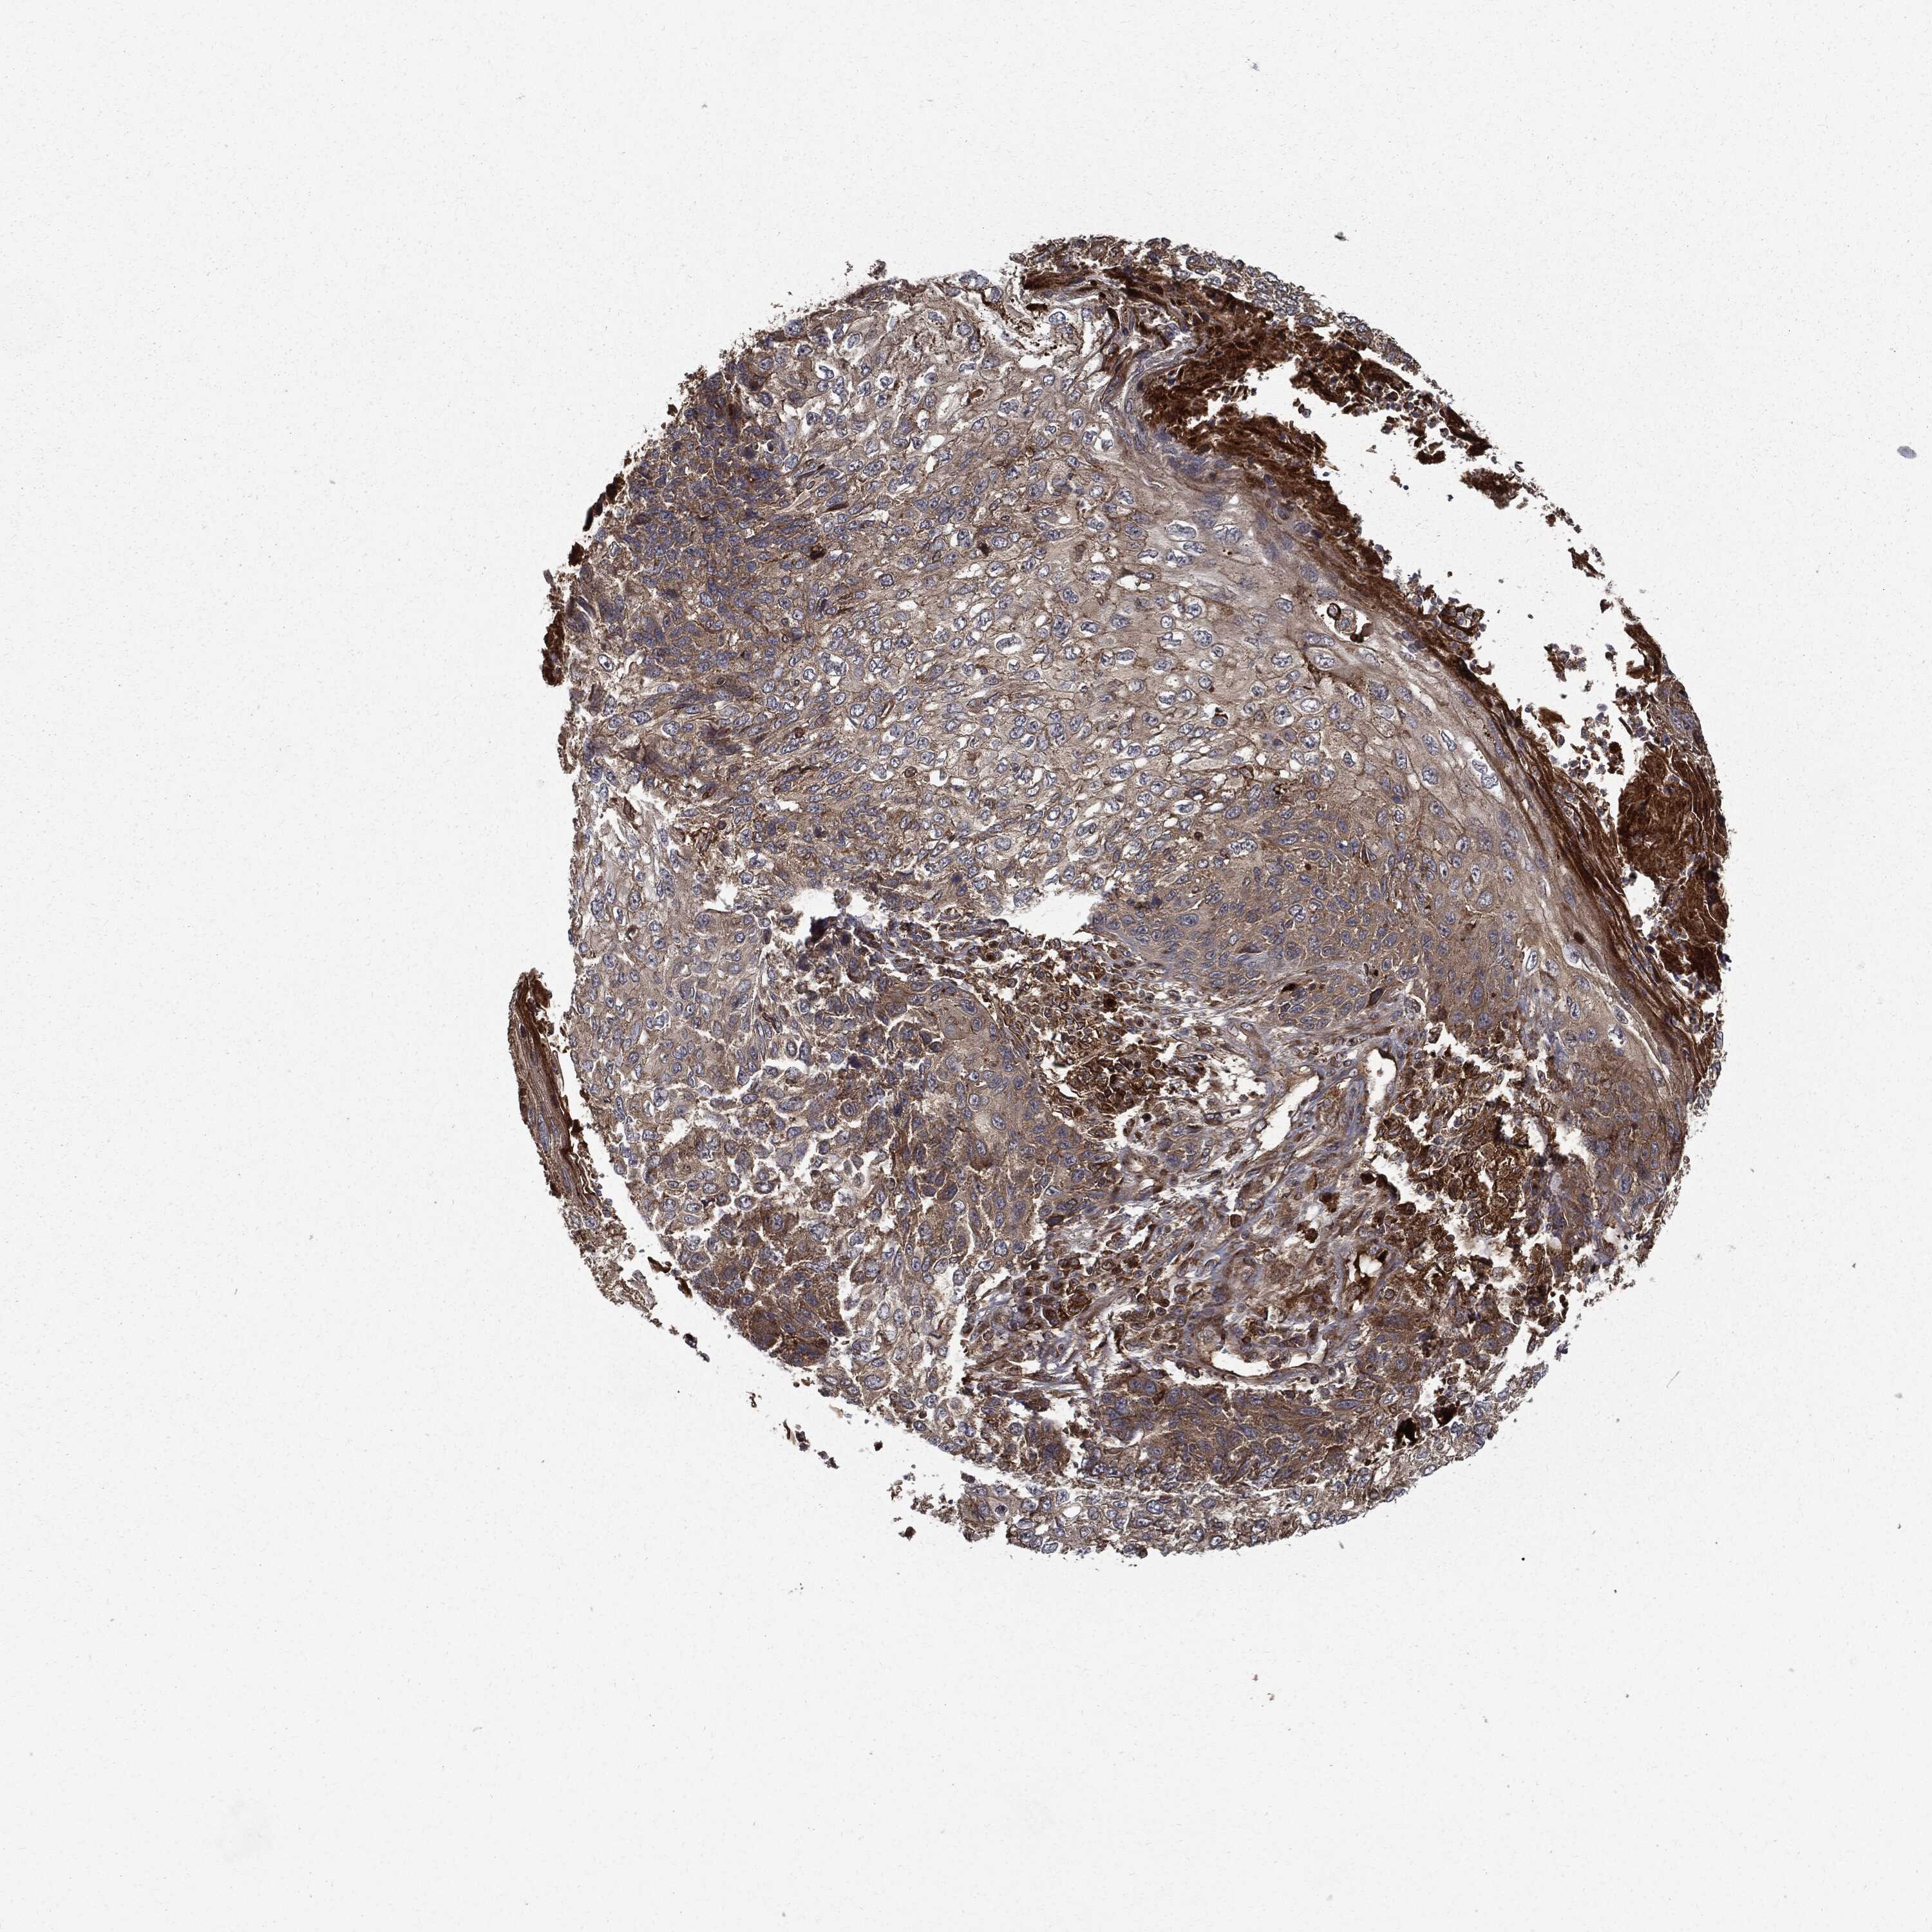

SKIN CANCER - Protein expressioni

A mouse-over function shows sample information and annotation data. Click on an image to view it in a full screen mode. Samples can be filtered based on level of antibody staining by selecting one or several of the following categories: high, medium, low and not detected. The assay and annotation is described here.

Each image is clickable and will lead to virtual microscopy that enables deeper exploration of all samples and also displays staining intensity scores, fraction scores and subcellular localization as well as patient and tissue information for each sample.

Antibody HPA026114

Antibody HPA051524

Antibody CAB002756

Staining

High

Medium

Low

Not detected

Intensity

Strong

Moderate

Weak

Negative

Quantity

>75%

75%-25%

<25%

None

Location

Nuclear

Cytoplasmic/membranous

Cytoplasmic/membranous,nuclear

Basal cell carcinoma

Squamous cell carcinoma, NOS

Squamous cell carcinoma, metastatic, NOS